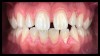

(12.) Intraoral photographs taken with a smartphone and an EALS device for orthodontic evaluation.

Figure 12

(13.) Intraoral photographs taken with a smartphone and an EALS device for orthodontic evaluation.

Figure 13